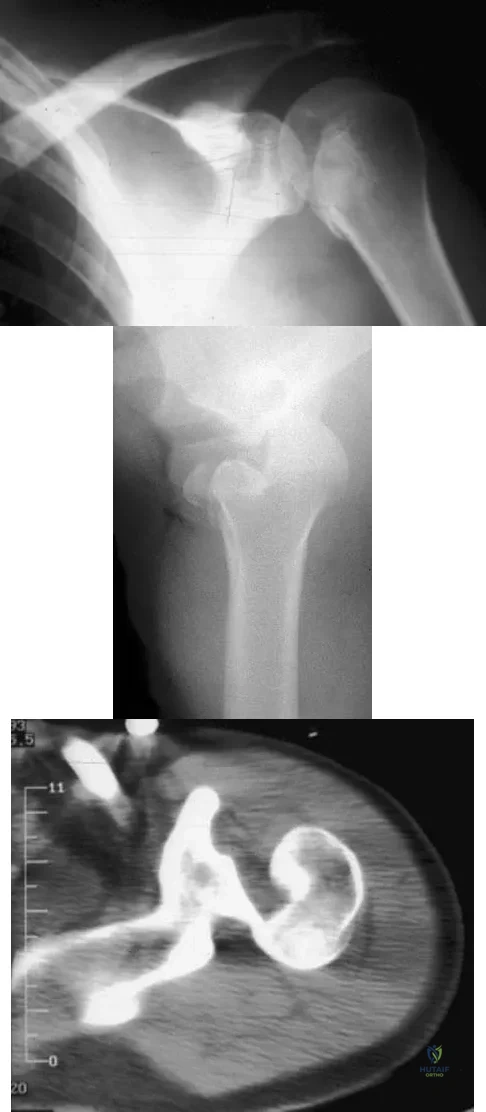

Question 46

A 21-year-old patient has had pain and a marked decrease in active and passive shoulder motion after having had a seizure 2 months ago as the result of alcohol abuse. Current AP and axillary radiographs and a CT scan are shown in Figures 26a through 26c. Management should consist of

Explanation